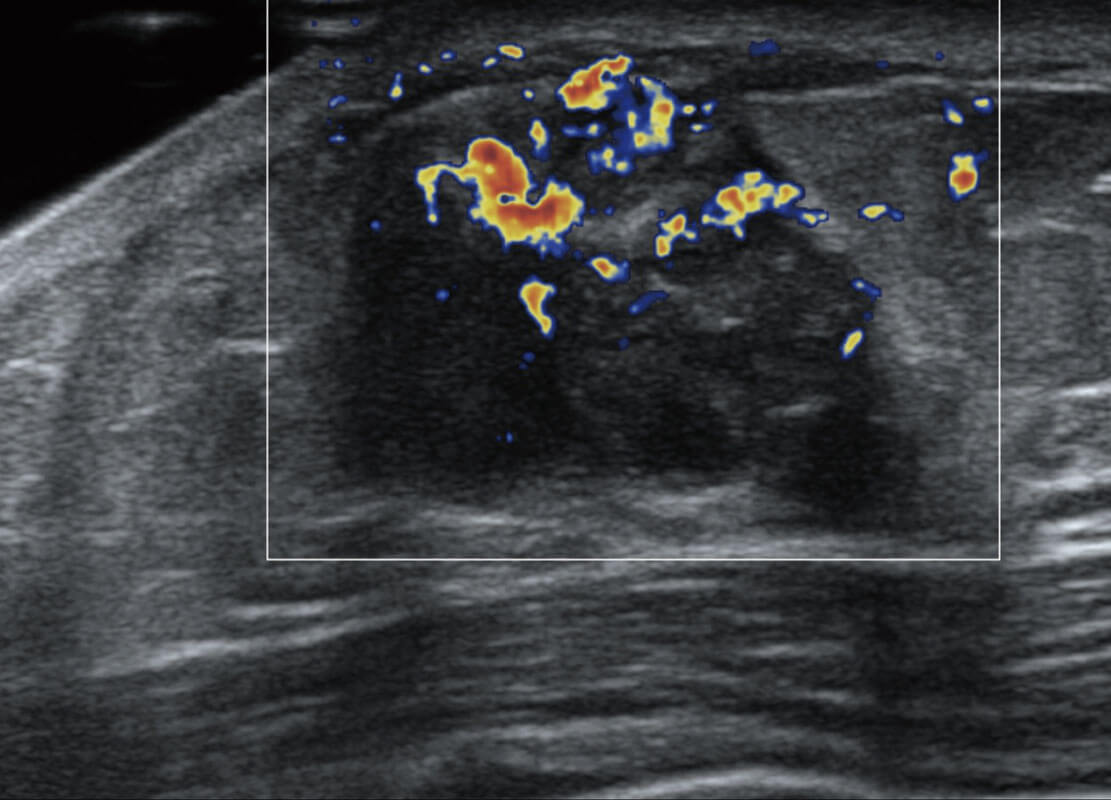

P60搭载宽频带线阵探头、宽景成像、弹性成像技术,为您提供乳腺应用方案。P60支持高频相控阵探头、线阵探头、腹部高频探头、腹部微凸探头等,丰富的探头群搭载敏感的彩色血流成像,适用于新生儿多种脏器检测要求,满足新生儿筛查需求。

乳腺导管癌